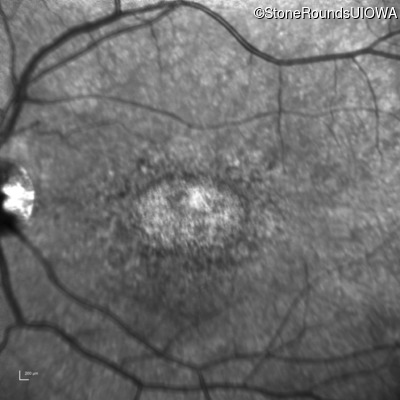

Age at visit: 29 years

This 29-year-old man had good vision until his early 20's. at which time he began to experience a slow reduction in his acuity. His driver's license was restricted at age 27.